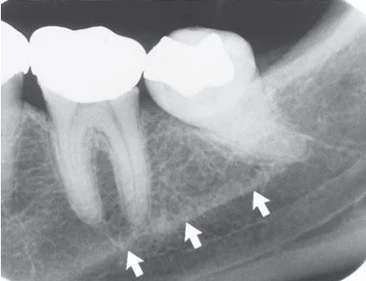

Gờ móng là một mào xương không đều nằm nên bề mặt trong của thân xương hàm dưới. Kéo dài từ vùng răng cối lớn thứ ba đến bờ dưới xương hàm dưới vùng cằm, nó đóng vai trò là chỗ bám của cơ hàm móng. Hình ảnh X quang chạy theo chiều nghiêng xuống và ra trước từ vùng răng cối lớn thứ ba đến vùng răng cối nhỏ, ở xấp xỉ mức chóp các răng sau.

Đôi khi hình ảnh chồng lên hình ảnh của các chân răng cối lớn. Bờ viền của hình ảnh gờ móng thường không rõ nhưng khá rộng với kích thước khác nhau. Tuy nhiên, cũng có thể thấy điều ngược lại, tại vị trí gờ tương đối đậm đặc và biên giới sắc nét.